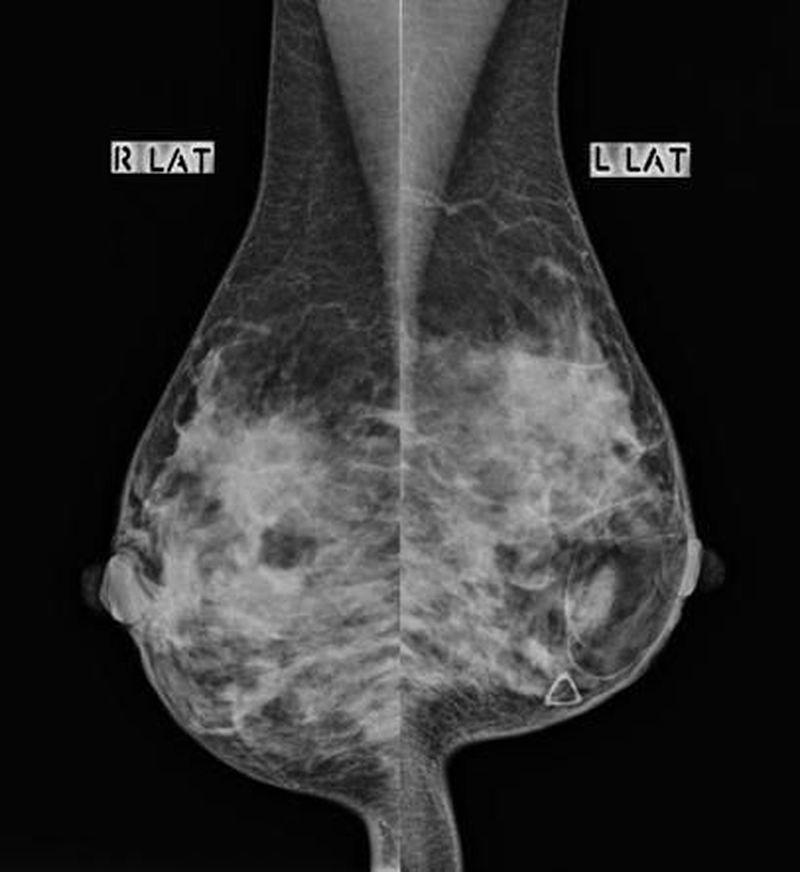

Mammography (Lateral) - “ Breast hamartomas are a benign and uncommon cause of a breast lump.